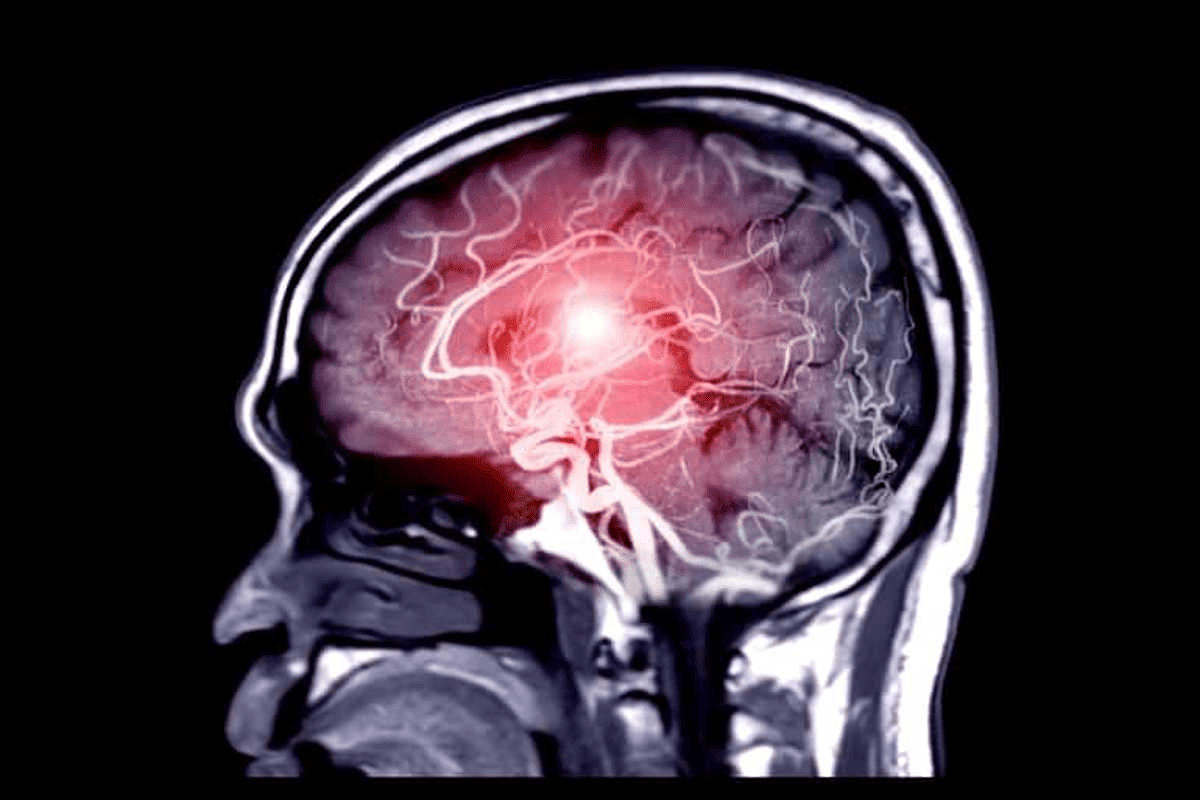

Imaging Techniques

Imaging is key in checking masses. Ultrasound is often the first choice because it’s safe and shows images in real-time. Magnetic Resonance Imaging (MRI) gives detailed views of soft tissues and is great for tricky cases.MRI can tell if a tumor is cancerous by showing signs of malignancy.

Computed Tomography (CT) scans show cross-sections and are good for finding masses in different parts of the body. X-rays help spot masses in bones or lungs.

Doctors use imaging like ultrasound and MRI, biopsies, and lab tests to check if a mass is malignant.